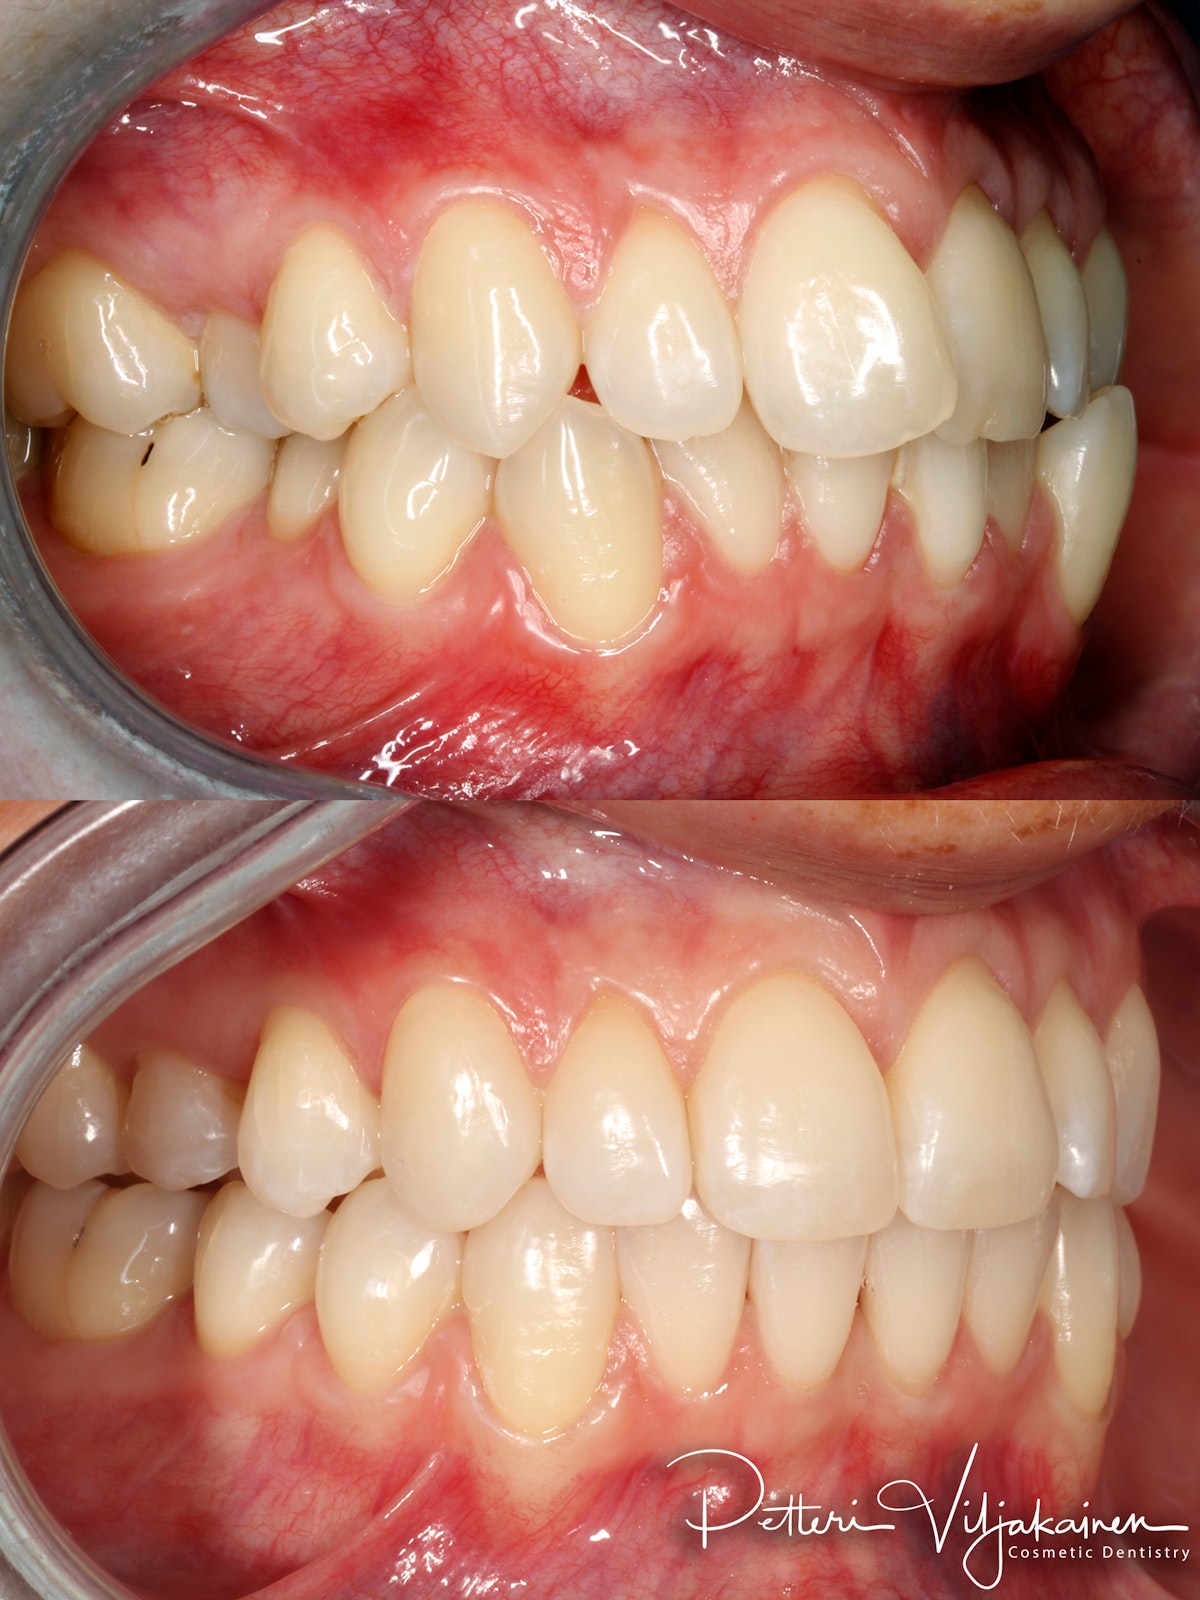

20kk hoito (Comprehensive).